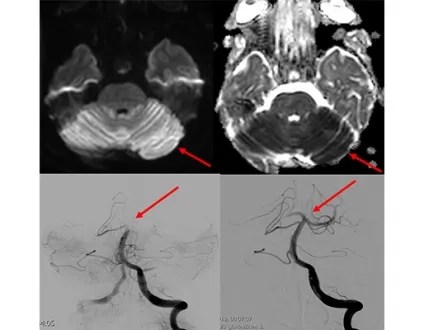

If stroke symptoms have not gone away for more than 6 hours, and if a blockage is detected in one of the main arteries in the brain, interventional radiology comes into play at this point. In the angiography unit, small pipes (catheters) are placed to the clot in the occluded artery in the brain by entering through the groin or the wrist, and the clot is mechanically removed and the blood flow in the occluded artery is restored to normal. When we look at the literature, it has been shown that mechanical removal of the clot, even in periods up to 6-24 hours after the emergence of stroke symptoms, allows the patient to continue his/her life independently or less dependently.

If the acute stroke is treated early, it becomes possible for patients to continue their lives without any disability or addiction. Some of our patients who come with sudden paralysis and speech disorders start to move their arms and legs after the clot is removed while they are still on the angiogram table, and their speech improves, they ask us questions, answer our questions, and return to work within a few days. These situations and moments we encounter in treatment are really pleasing.